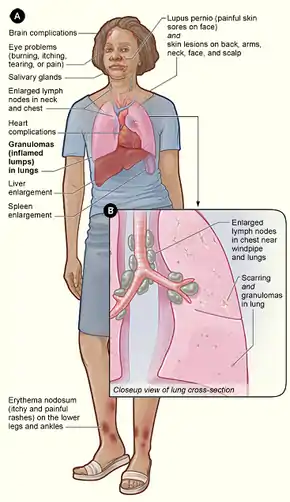

| |

| Chest X-ray showing the typical nodularity of sarcoidosis, predominantly in the hila of the lungs. | |

Sarcoidosis (also known as Besnier–Boeck–Schaumann disease) is a disease involving abnormal collections of inflammatory cells that form lumps known as granulomata.[2] The disease usually begins in the lungs, skin, or lymph nodes.[2] Less commonly affected are the eyes, liver, heart, and brain, though any organ can be affected.[2] The signs and symptoms depend on the organ involved.[2] Often, no, or only mild, symptoms are seen.[2] When it affects the lungs, wheezing, coughing, shortness of breath, or chest pain may occur.[3] Some may have Löfgren syndrome with fever, large lymph nodes, arthritis, and a rash known as erythema nodosum.[2]

Sarcoidosis is a systemic inflammatory disease that can affect any organ, although it can be asymptomatic and is discovered by accident in about 5% of cases.[17] Common symptoms, which tend to be vague, include fatigue (unrelieved by sleep; occurs in up to 85% of cases [18]), lack of energy, weight loss, joint aches and pains (which occur in about 70% of cases),[19] arthritis (14–38% of cases), dry eyes, swelling of the knees, blurry vision, shortness of breath, a dry, hacking cough, or skin lesions.[20][21][22][23] Less commonly, people may cough up blood.[20] Sarcoidosis is also accompanied by psychological distress and symptoms of anxiety and depression, which are also associated with fatigue.[24] The cutaneous symptoms vary, and range from rashes and noduli (small bumps) to erythema nodosum, granuloma annulare, or lupus pernio. Sarcoidosis and cancer may mimic one another, making the distinction difficult.[25]

The combination of erythema nodosum, bilateral hilar lymphadenopathy, and joint pain is called Löfgren syndrome, which has a relatively good prognosis.[20] This form of the disease occurs significantly more often in Scandinavian patients than in those of non-Scandinavian origin.[26]

Localization to the lungs is by far the most common manifestation of sarcoidosis.[27] At least 90% of those affected experience lung involvement.[28] Overall, about 50% develop permanent pulmonary abnormalities, and 5 to 15% have progressive fibrosis of the lung parenchyma. Sarcoidosis of the lung is primarily an interstitial lung disease in which the inflammatory process involves the alveoli, small bronchi, and small blood vessels.[29] In acute and subacute cases, physical examination usually reveals dry crackles.[28] At least 5% of cases include pulmonary arterial hypertension.[28][30] The upper respiratory tract (including the larynx, pharynx, and sinuses) may be affected, which occurs in between 5 and 10% of cases.[31]

Skin

Sarcoidosis involves the skin in between 9 and 37% of cases and is more common in African Americans than in European Americans.[28] The skin is the second-most commonly affected organ after the lungs.[33] The most common lesions are erythema nodosum, plaques, maculopapular eruptions, subcutaneous nodules, and lupus pernio.[33] Treatment is not required, since the lesions usually resolve spontaneously in 2–4 weeks. Although it may be disfiguring, cutaneous sarcoidosis rarely causes major problems.[28][34][35] Sarcoidosis of the scalp presents with diffuse or patchy hair loss.[36][37]